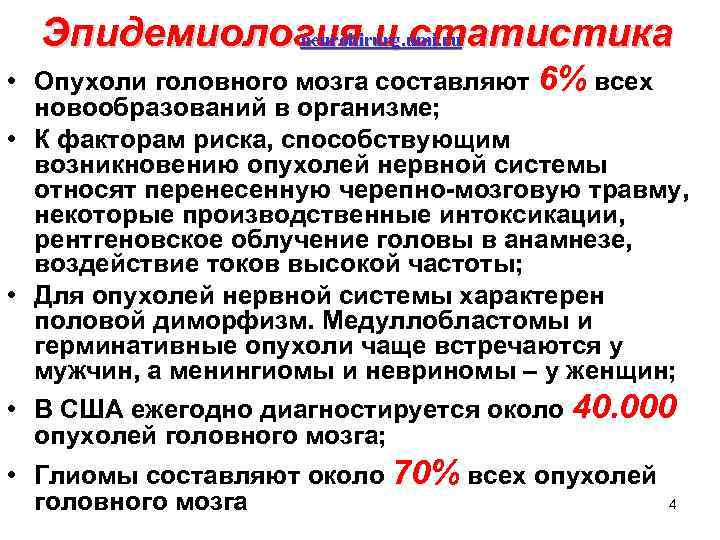

neurohirurg. umi. ru Эпидемиология и статистика • Опухоли головного мозга составляют 6% всех новообразований в организме; • К факторам риска, способствующим возникновению опухолей нервной системы относят перенесенную черепно мозговую травму, некоторые производственные интоксикации, рентгеновское облучение головы в анамнезе, воздействие токов высокой частоты; • Для опухолей нервной системы характерен половой диморфизм. Медуллобластомы и герминативные опухоли чаще встречаются у мужчин, а менингиомы и невриномы – у женщин; • В США ежегодно диагностируется около 40. 000 опухолей головного мозга; • Глиомы составляют около 70% всех опухолей 4 головного мозга